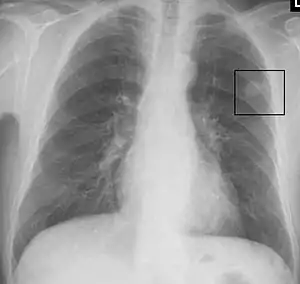

Often discovered unintentionally on a chest x-ray, a single nodule in the lung requires assessment to exclude cancer.[9]